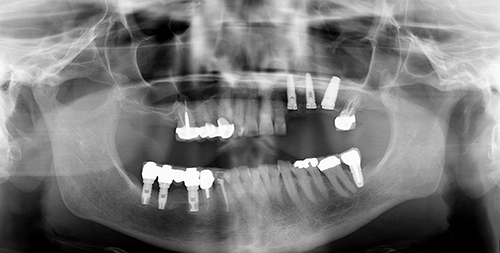

Dental implant therapy is the closest thing to the natural dentition practitioners can provide for their patients. Diagnosis and treatment planning, in conjunction with new technologies, help determine the best placement and use of dental implants. It is good to consider the surgical and restorative needs of the patient, as well as the risks, long-term prognosis and durability of the treatment. When issues arise with dental implant therapy, it is important to be familiar with potential complications. When there are complications, it is equally as important to know how to address them. This course provides state of the art knowledge about dental implant therapy that will help lead to better care for your patients.